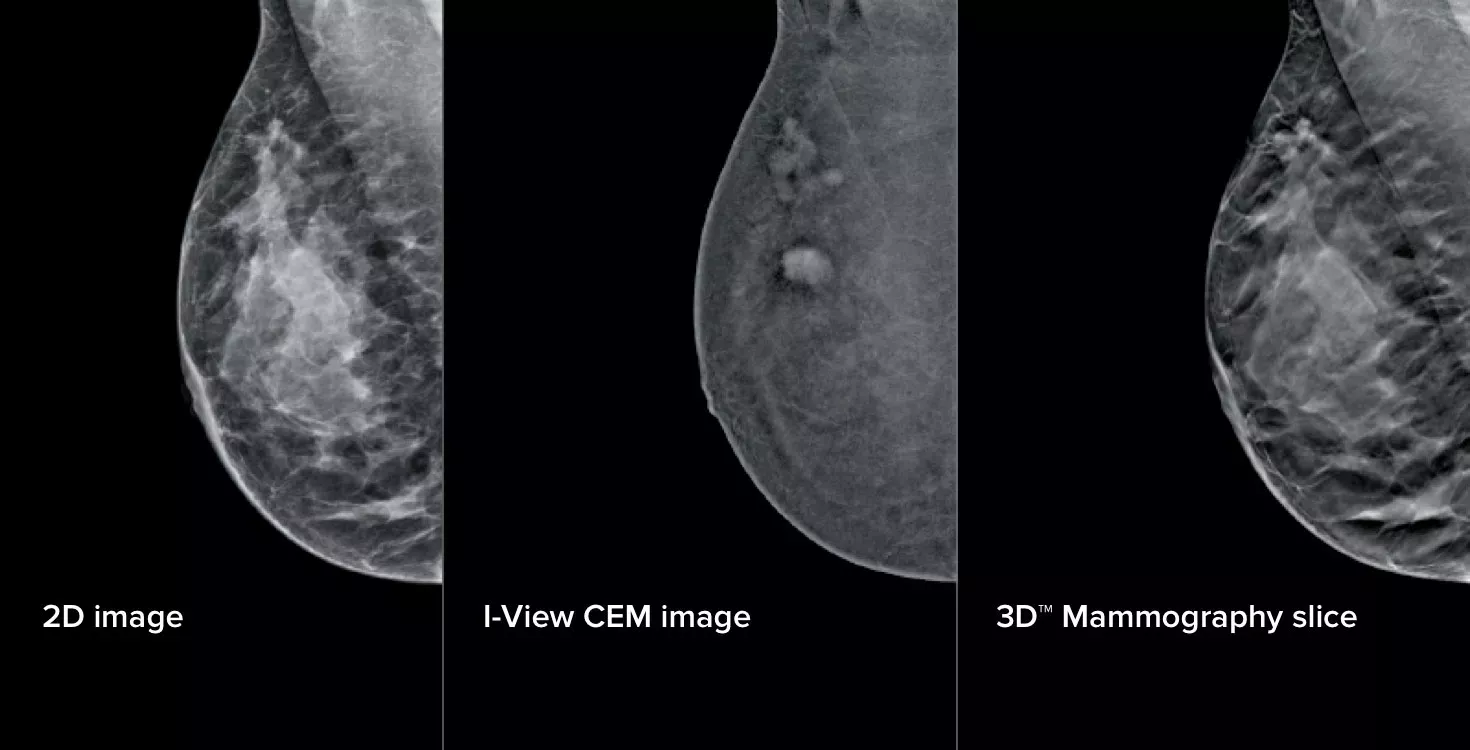

Affirm Contrast Biopsy software allows targeting and acquisition of tissue samples in lesions identified on prior CEM exams, where a correlate may not be found using tomosynthesis or ultrasound.

During a contrast enhanced mammogram, following iodine injection, lesions are localized using a scout view and the 15-degree image pairs.

Turn the invisible into visible by using functional imaging.

Hologic’s powerful contrast mammography and biopsy solutions, including the Affirm® upright biopsy system, I-View® 2.0 Contrast Enhanced mammography software, and Affirm® contrast biopsy software, provide smart tools to confidently guide the clinical pathway through screening to diagnosis and biopsy.